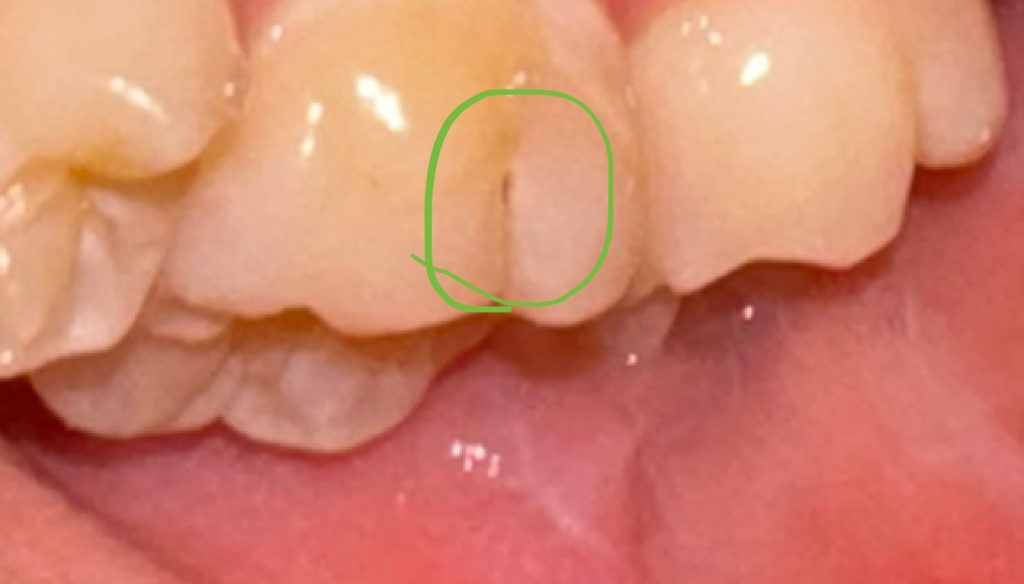

치아 옆면이 약간 검은듯한데요

충치일까요? 혹은 그냥 틈일까요?

제 치아가 다른치아들도 모두 틈이 있는편이긴 한데요

저게 충치인지 혹은 그냥 틈인지 모르겠어요ㅠㅠ

사진으로 보았을 때는 충치일 가능성이 매우 큽니다. 해당 부분을 제거하면 생각보다 깊게 충치가 있을 것으로 보이며 이는 제거를 하고 적절한 치료를 하는 것이 좋습니다.

초기 충치라고 여겨집니다. 다만, 치료가 필요한 정도는 아닐 것 같고 확인차 x-ray를 찍어보면 좋을 것 같습니다.

해당 부는 최 모양이 안쪽으로 파여있기 때문에 음식물이 잘 남아 있게 되어 충치가 생기기 쉬운 부위입니다. 충치가 있다면 충치를 치료하는 것이 좋으며 그렇지 않다면 홈을 메꿔서 이물질이 안으로 들어가지 않도록 하는 것이 좋습니다.

치아의 바깥쪽 부분에 약간의 충치가 잇는거 같습니다. 치과에 가셔서 검진후 진행되는 충치라면 치료를 받으시면될것같습니다.

미세하게 충치가 발생한 것으로 보입니다. 치과에 방문하여 보다 정확히 확인후 치료를 받길 권합니다.